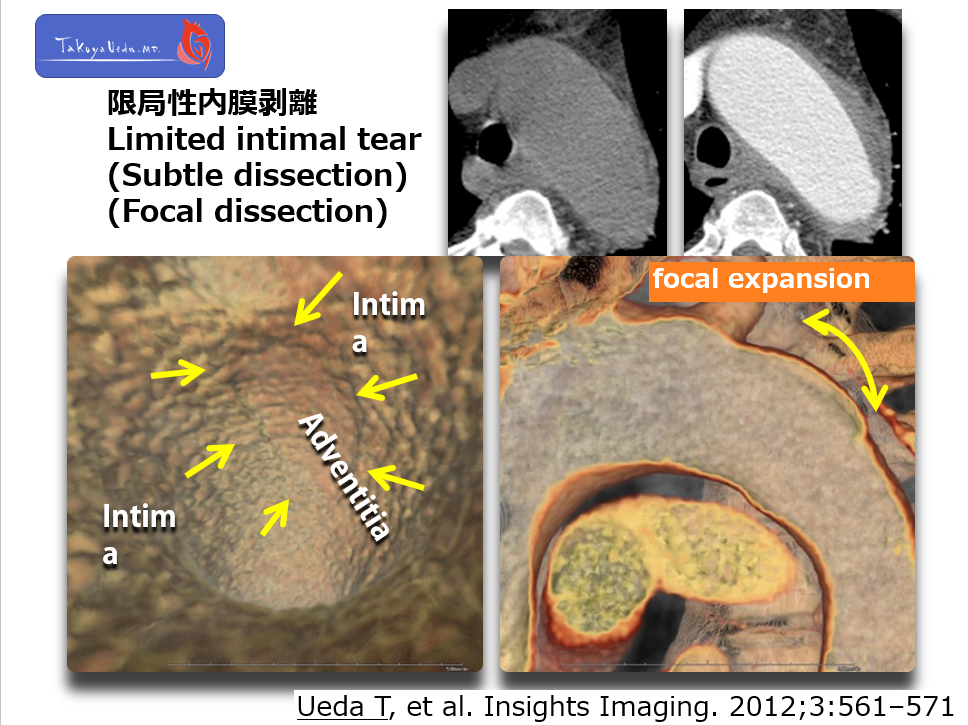

On 3D image and vessel luminal view, You see focal bulge of aortic wall is visualized. Such focal expansion is not common in Ath. An.

Once you are aware of this condition, you can diagnose limited intimal tear using ECG-gated technique.

I reported that the risk of rupture is much higher than common An.